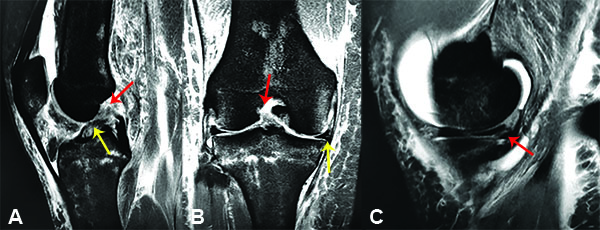

Paciente femenino de 44 años, esquiadora recreativa, que consulta a nuestra institución el 22 de julio del año 2018, por un cuadro de dolor, limitación funcional e inestabilidad anterior de rodilla derecha posterior a un traumatismo deportivo (ski en nieve) de 1 semana de evolución. El examen físico reveló una prueba de Lachman positiva (++), pivot shift positivo (+), derrame articular con choque rotuliano positivo (+++) y test de McMurray (+) para menisco interno. El diagnóstico de lesión completa tipo I (avulsión femoral) del LCA según la clasificación de Sherman28 (fig. 1) y lesión vertical longitudinal periférica del cuerno posterior del menisco interno, se confirmó por resonancia magnética nuclear (RMN) de rodilla (fig. 2).

Figura 2: A) Imagen que muestra un corte sagital de Resonancia Magnética Nuclear (RMN) de rodilla donde se observa la avulsión proximal y el remanente del LCA. Flecha Roja (FR): Avulsión Femoral del LCA. Flecha Amarilla (FA): Remanente Completo del LCA. B) Imagen que muestra un corte coronal de Resonancia Magnética Nuclear (RMN) de rodilla derecha donde se observa la avulsión del LCA en su inserción proximal femoral y la lesión del Menisco interno. FR: Avulsión femoral del LCA. FA: Lesión del menisco interno. C) Imagen que muestra un corte sagital de Resonancia Magnética Nuclear (RMN) de rodilla derecha donde se observa la lesión del cuerno posterior del Menisco interno. FR: Lesión del cuerno Post. del Menisco Int.